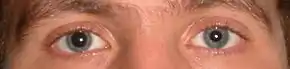

Head trauma recipients are initially assessed to exclude a more severe emergency such as an intracranial hemorrhage or other serious head or neck injuries. This includes the "ABCs" (airway, breathing, circulation) and stabilization of the cervical spine which is assumed to be injured in any athlete who is found to be unconscious after head or neck injury. Indications that screening for more serious injury is needed include 'red flag symptoms' or 'concussion danger signs': worsening headaches, persisting vomiting, increasing disorientation or a deteriorating level of consciousness, seizures, and unequal pupil size.[10][62][63][64] Those with such symptoms, or those who are at higher risk of a more serious brain injury, require an emergency medical assessment.[10] Brain imaging such as a CT scan or MRI may be suggested, but should be avoided unless there are progressive neurological symptoms, focal neurological findings, or concern of skull fracture on exam.[65]

Measurement of predictive visual tracking is being studied as a screening technique to identify mild traumatic brain injury. A head-mounted display unit with eye-tracking capability shows a moving object in a predictive pattern for the person to follow with their eyes. People without brain injury will be able to track the moving object with smooth pursuit eye movements and correct trajectory while it is hypothesized that those with mild traumatic brain injury cannot.[142]